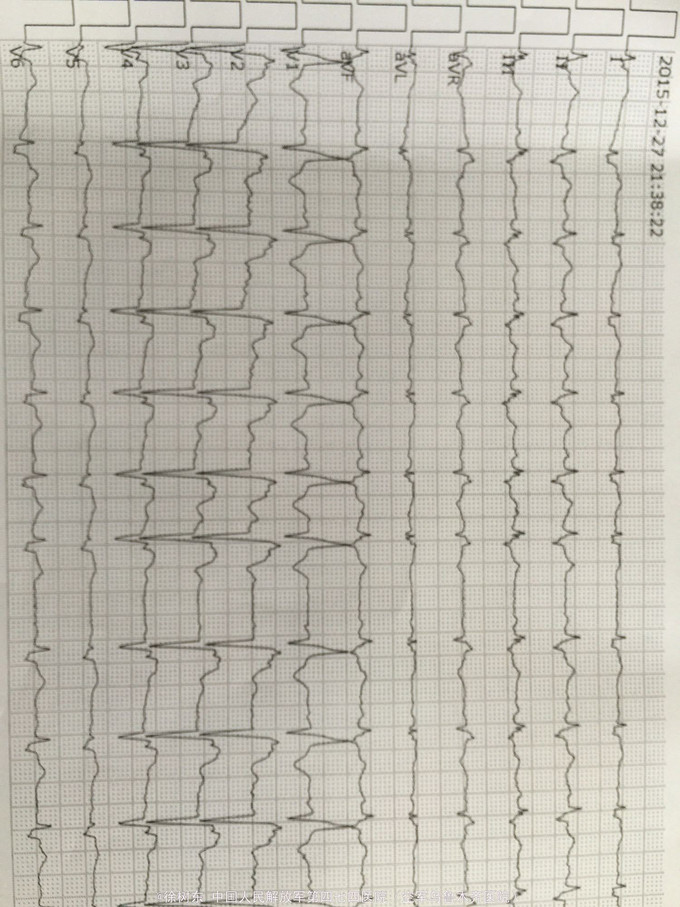

患者女、87岁、因突发恶心、上腹胀不适10小时入院。患者于12月27日中午12点突发恶心、呕吐不适,就诊社区给予左氧静点后无改善,晚间19点再次就诊后查心电图提示急性广泛前壁心肌梗死,其后转我院行PCI手术治疗。

冠心病急性广泛前壁心肌梗塞 阵发性室性心动过速 心室颤动